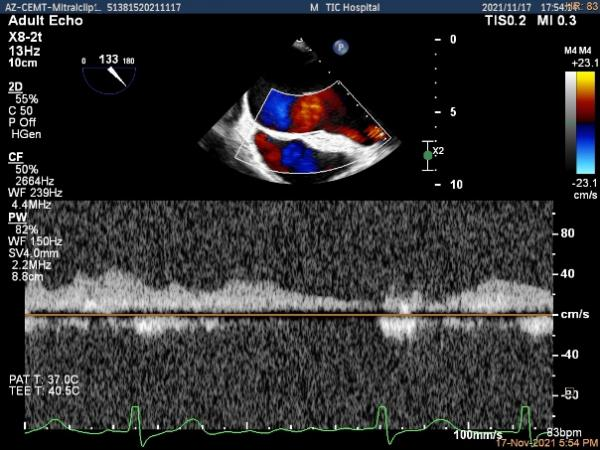

肺静脉血流频谱逐渐恢复正向,后测量平均跨瓣压差:2mmHg

肺静脉血流频谱恢复正向

二尖瓣瓣口平均跨瓣压差:3mmHg